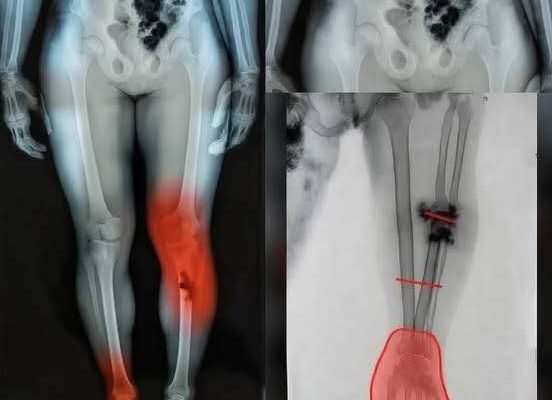

At first, people thought it was just another phase of recovery—aches, fatigue, maybe a bit of lingering discomfort. But then something different started happening. Individuals began reporting unusual pain in specific areas, particularly in the legs and lower body, symptoms that didn’t quite match what they had been told to expect. The pattern was subtle at first, but it quickly caught attention.

Medical professionals began looking deeper, trying to understand whether these cases were isolated or part of a broader trend. Some patients described a burning sensation, others a deep ache that seemed to come and go without warning. While not everyone experienced it, the consistency in certain reports was enough to raise concern and prompt further investigation.